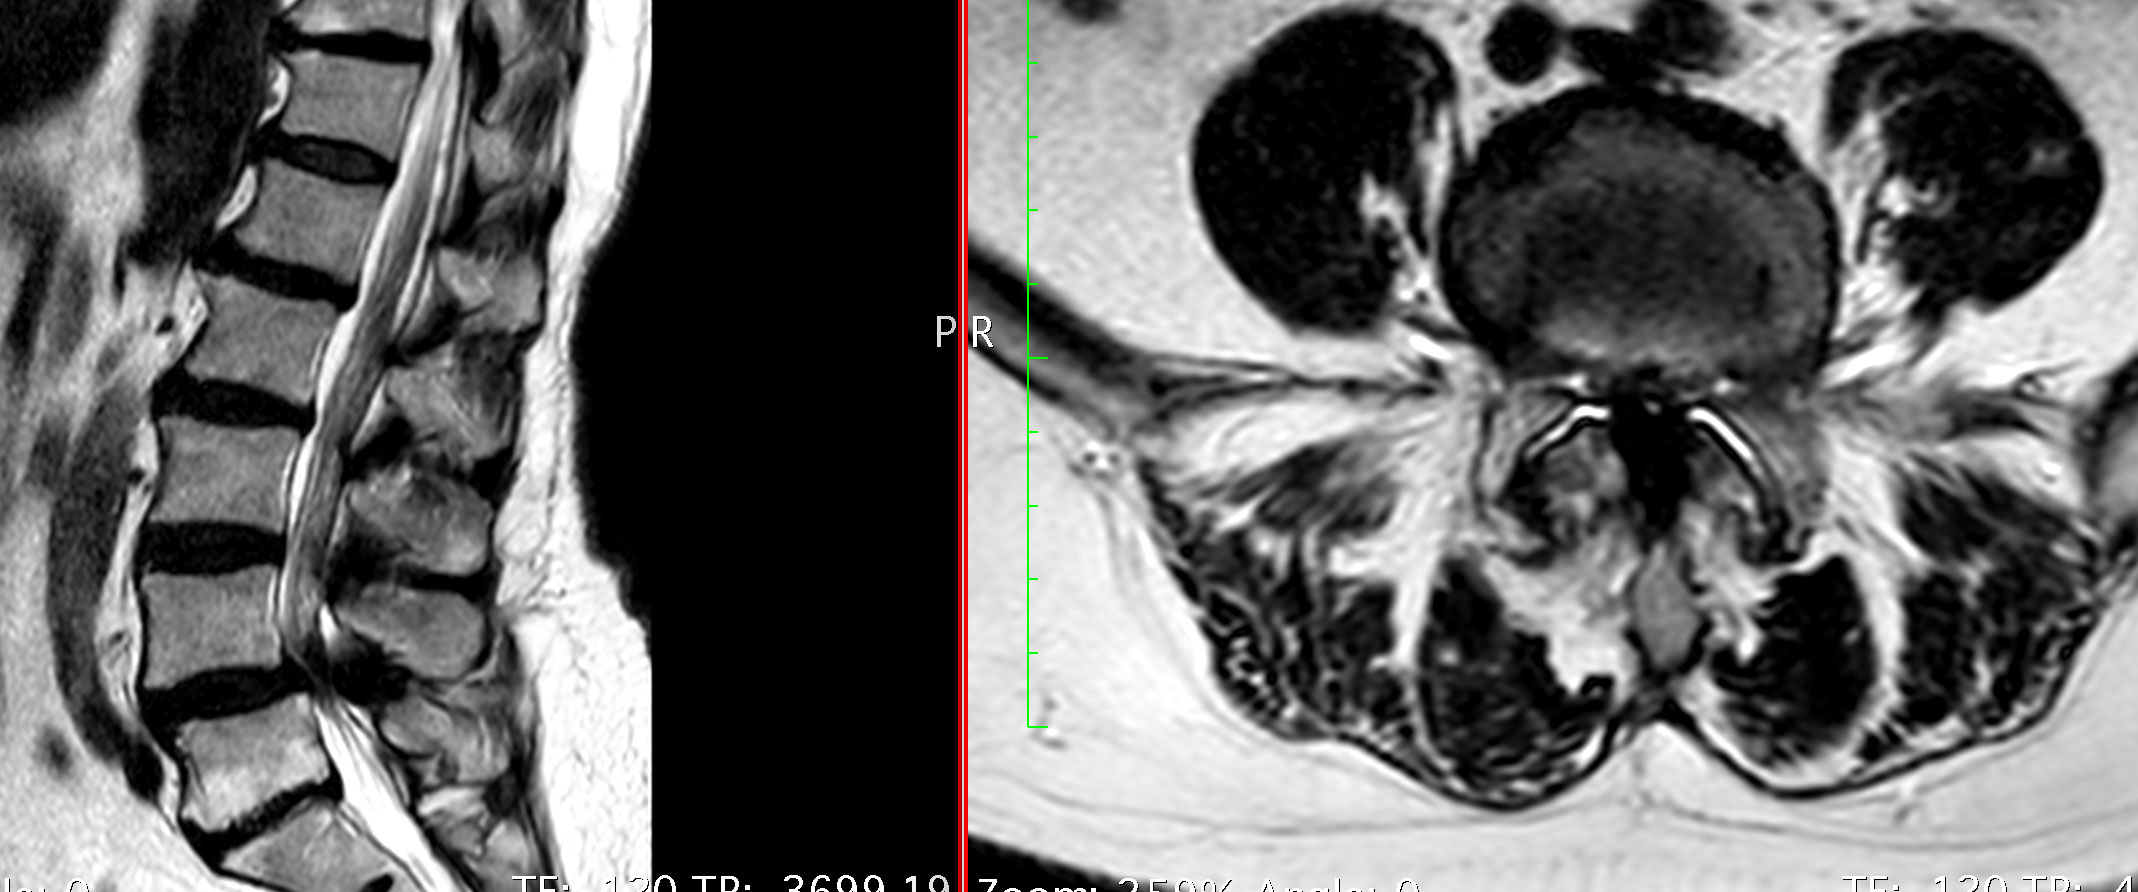

Estenosis de Canal

La estenosis de canal se produce cuando se reduce el espacio que rodea a la médula espinal. Esto genera una presión sobre las estructuras internas que puede producir dolor lumbar y/o ciático y claudicación a la marcha.